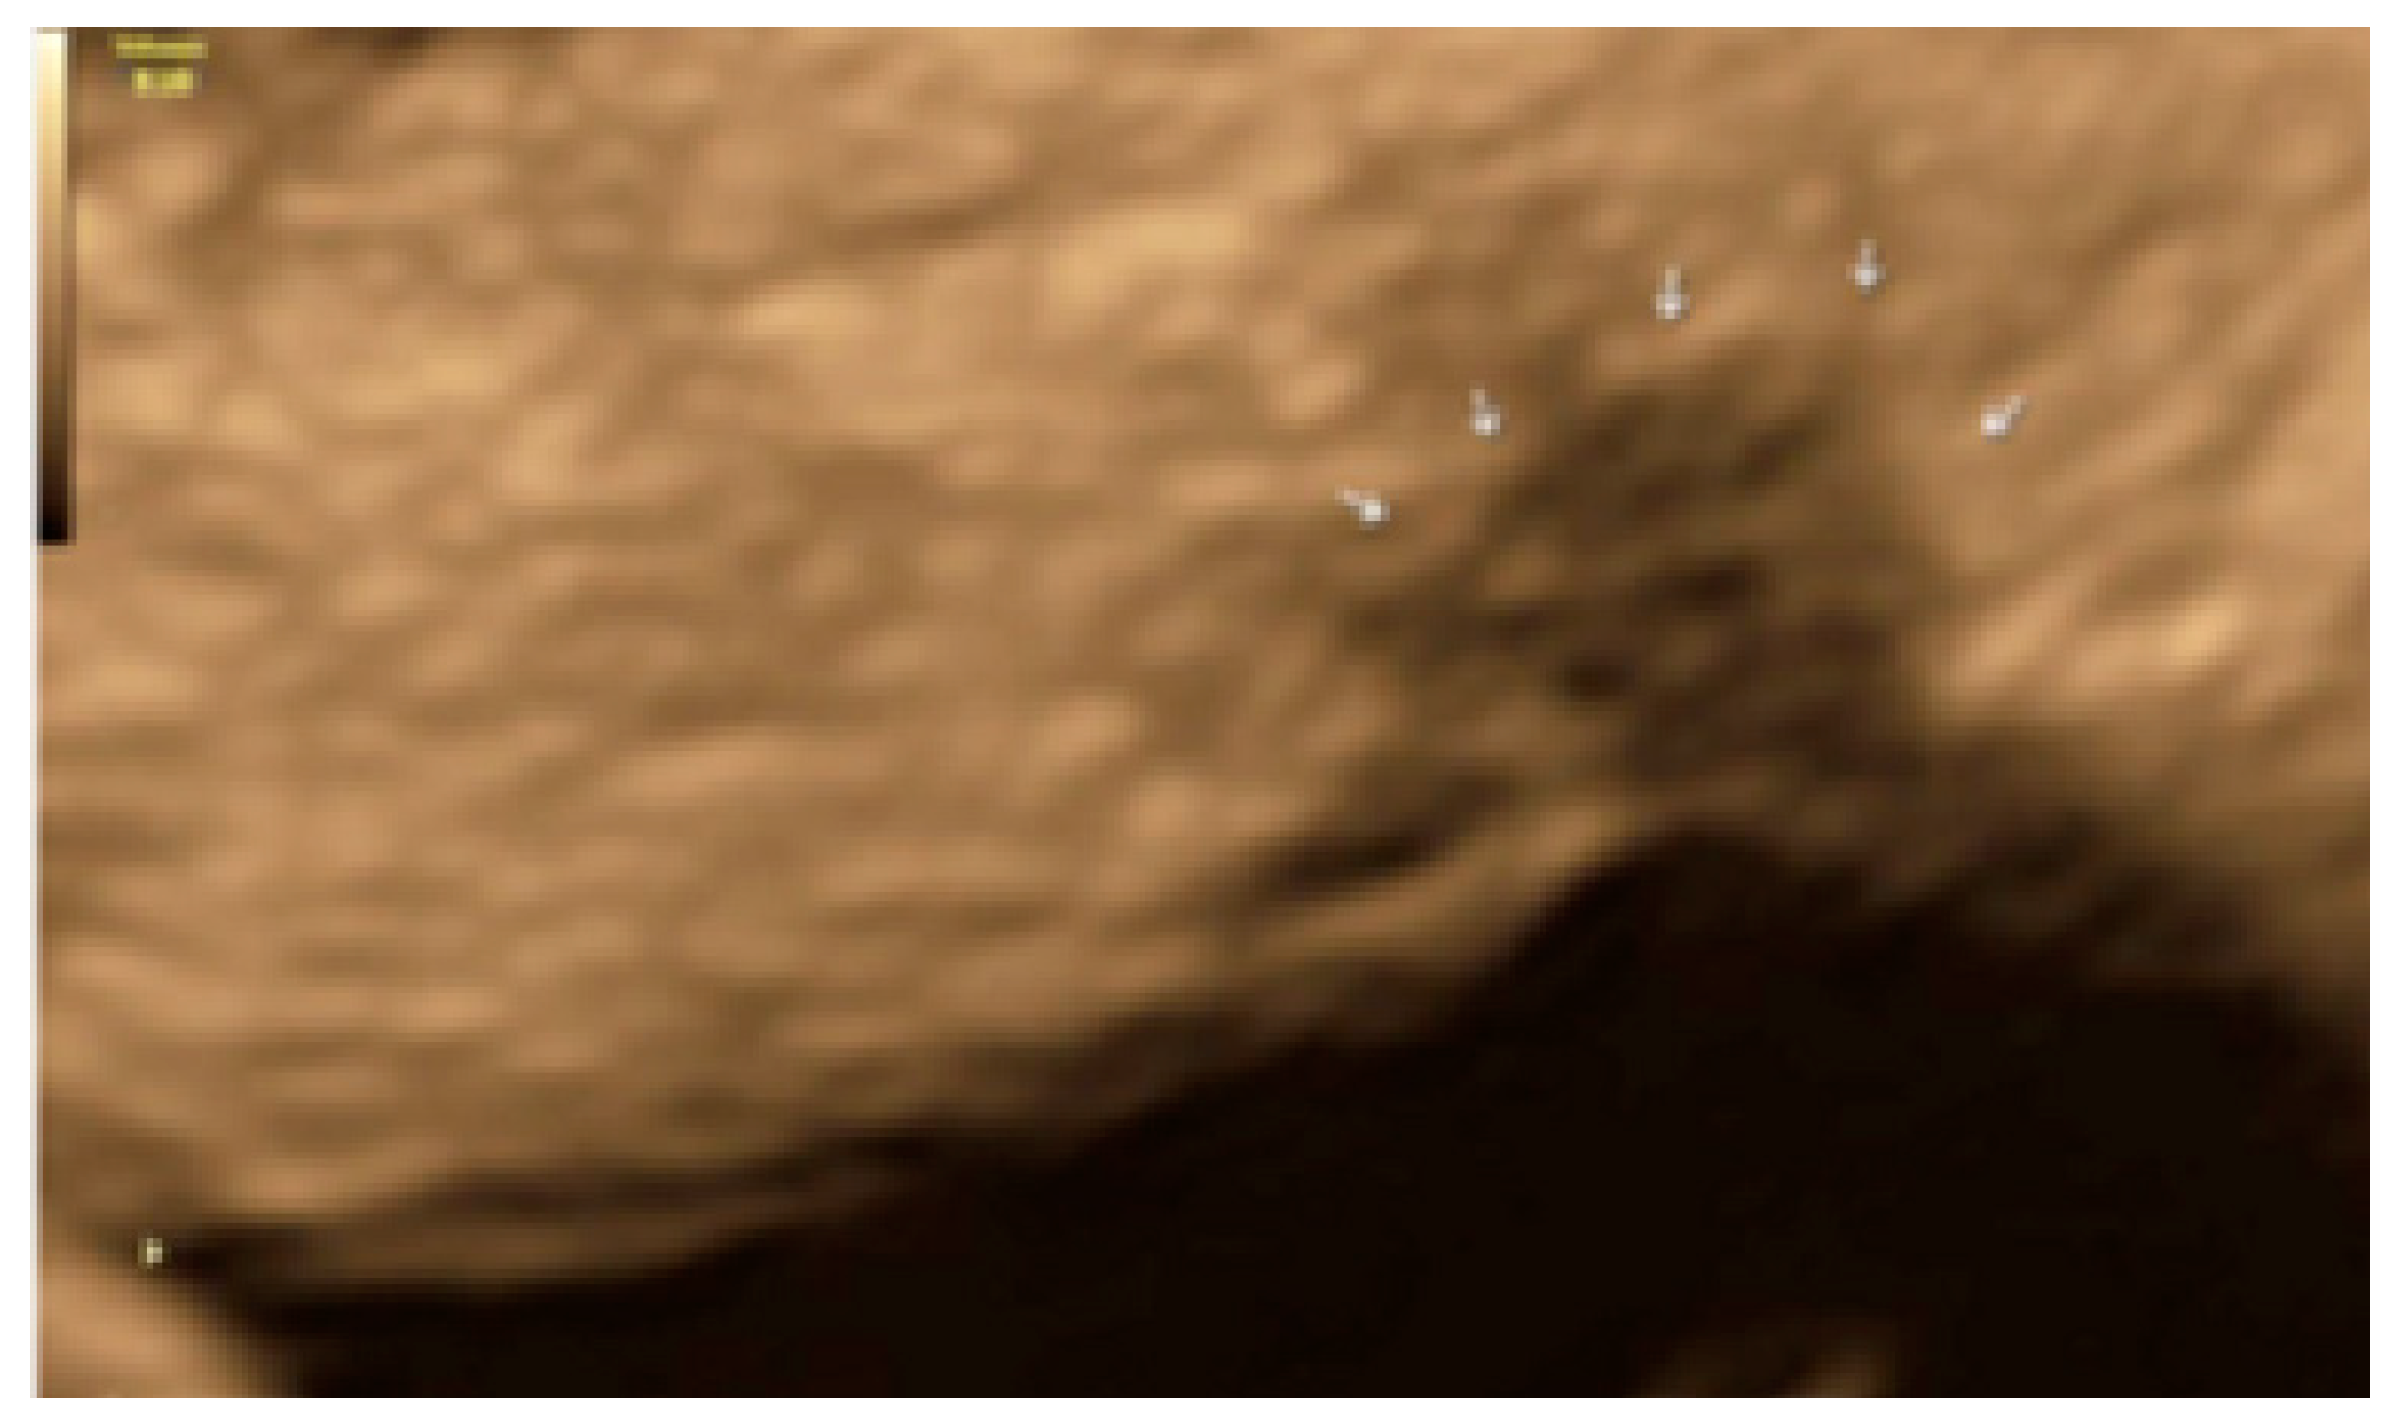

- The presence of velamentous (filmy) adhesions associated to the lesion (we called this a “veil”).